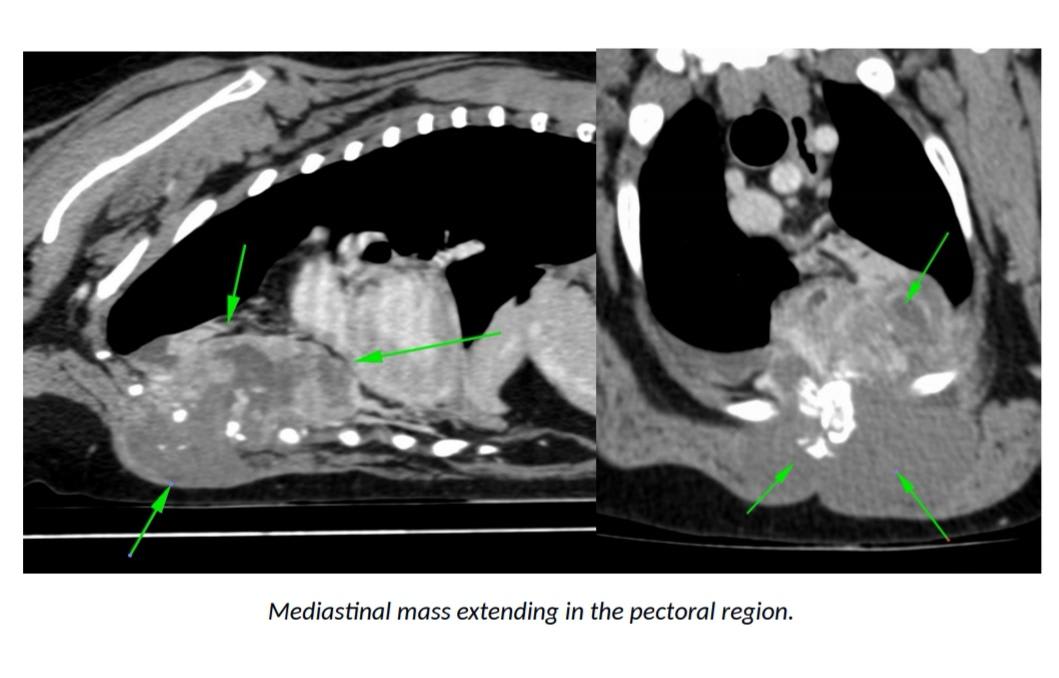

Hello. Yogi was out through many procedures in March/April. The tissue biospsys were not conclusive but likely cancer was the outcome and that he would go downhill quickly and to bring him back for pain medication when he did. It is November now and he is as normal as a year ago. Walking, running, eating well and no pain. Is this normal or could the diagnosis be something completely different. He is getting new lumps on his body but seems very comfortable. An experienced opinion will be great

Thanks for using Petco Pet Education Center, formerly Petcoach! I would agree that the mediastinal mass is very evident and I would also be very suspicious that it is in fact cancer even if the biopsy did not show that. Sometimes dogs appear to be comfortable even when they are in pain. These new lumps you describe could be somewhat related to this or may be unrelated. I think it would be ideal to have Yogi reevaluated to see if the mass has progressed and if the nodules in the lungs (which likely represent spread of the tumor) have also progressed. I would maintain him on pain control medications even if he does not appear to be obviously in pain. Good luck and have a great day!